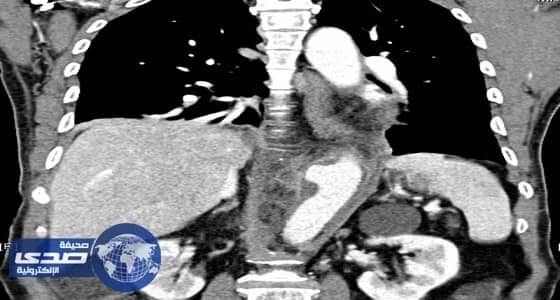

نجح فريق طبي بقسم جراحة الأوعية الدموية والتداخلية بمستشفى النور التخصصي بمكة المكرّمة، في إجراء عملية جراحية ناجحة لإزالة الشريان الأورطى الملتهب ووضع شريان صناعي لوافد من الجنسية الإندونيسية، يبلغ من العمر خمسين عاماً مستغرقاً 12ساعة في العملية .

وقال رئيس قسم جراحة الأوعية الدموية التداخلية الدكتور محمد بن عمر بافرج؛ الذي أجرى العملية، أن المريض حضر إلى قسم الطوارئ والحوادث وهو يعاني آلاماً شديدة بالظهر والبطن، وبعد الفحص السريري والأشعة المقطعية اتضح وجود التهاب شديد مع تجمُع صديدي محاط بالأورطى العلوي للبطن؛ ما استلزم ضرورة التدخّل الجراحي.